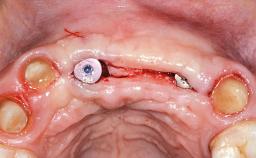

Replacement of Four Incisors with a Fixed Partial Denture on Two Narrow-Neck Implants after Implant Failure

| Type of Implants | One-Piece|Reduced-Diameter |

| Bone Augmentation | Horizontal|Staged|Vertical |

| Augmentation Materials | Autogenous block(s)|Xenogenous|Membrane |